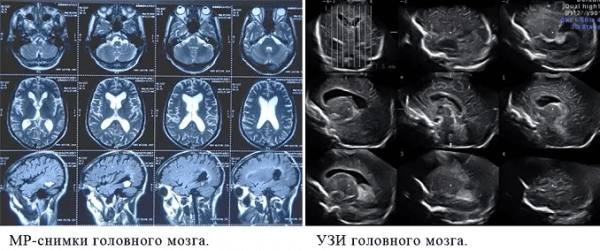

Есть некоторые органы, обследование которых рекомендуют начинать с проведения МРТ. В частности, речь идет о головного мозге. С помощью УЗИ оценить его строение у взрослых очень проблематично, т. к. со всех сторон мозг заключен в череп, который практически не пропускает ультразвуковых волн. Для МРТ это не является препятствием.